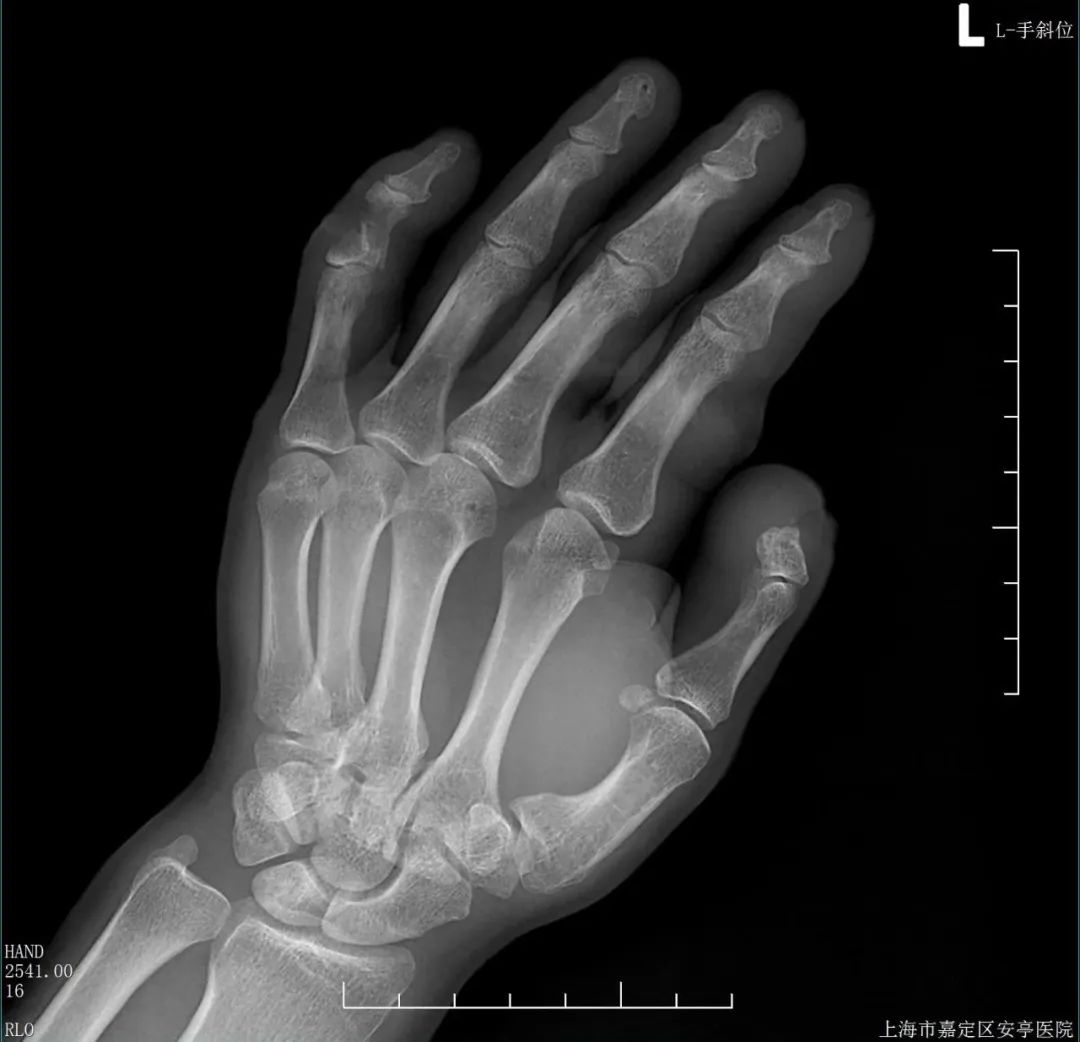

近日,嘉定区安亭医院骨科成功完成一例断肢再植手术,为一名“70后”市民保住了左手断离的手指。

半个月前,杨先生不慎被电锯锯到左手,导致左手小指、中指伸肌腱断裂,食指不完全断离、皮肉粘连,被送往安亭医院急救。

经过清创以及克氏针髓内固定骨折端、肌腱后,在高倍显微镜下,韩爽对着细如发丝的血管“穿针引线”,逐步修复指动脉、静脉以及指神经。经过3个小时的“精雕细琢”,离断的血管、神经、肌腱、指骨和皮肤终于一一对接。